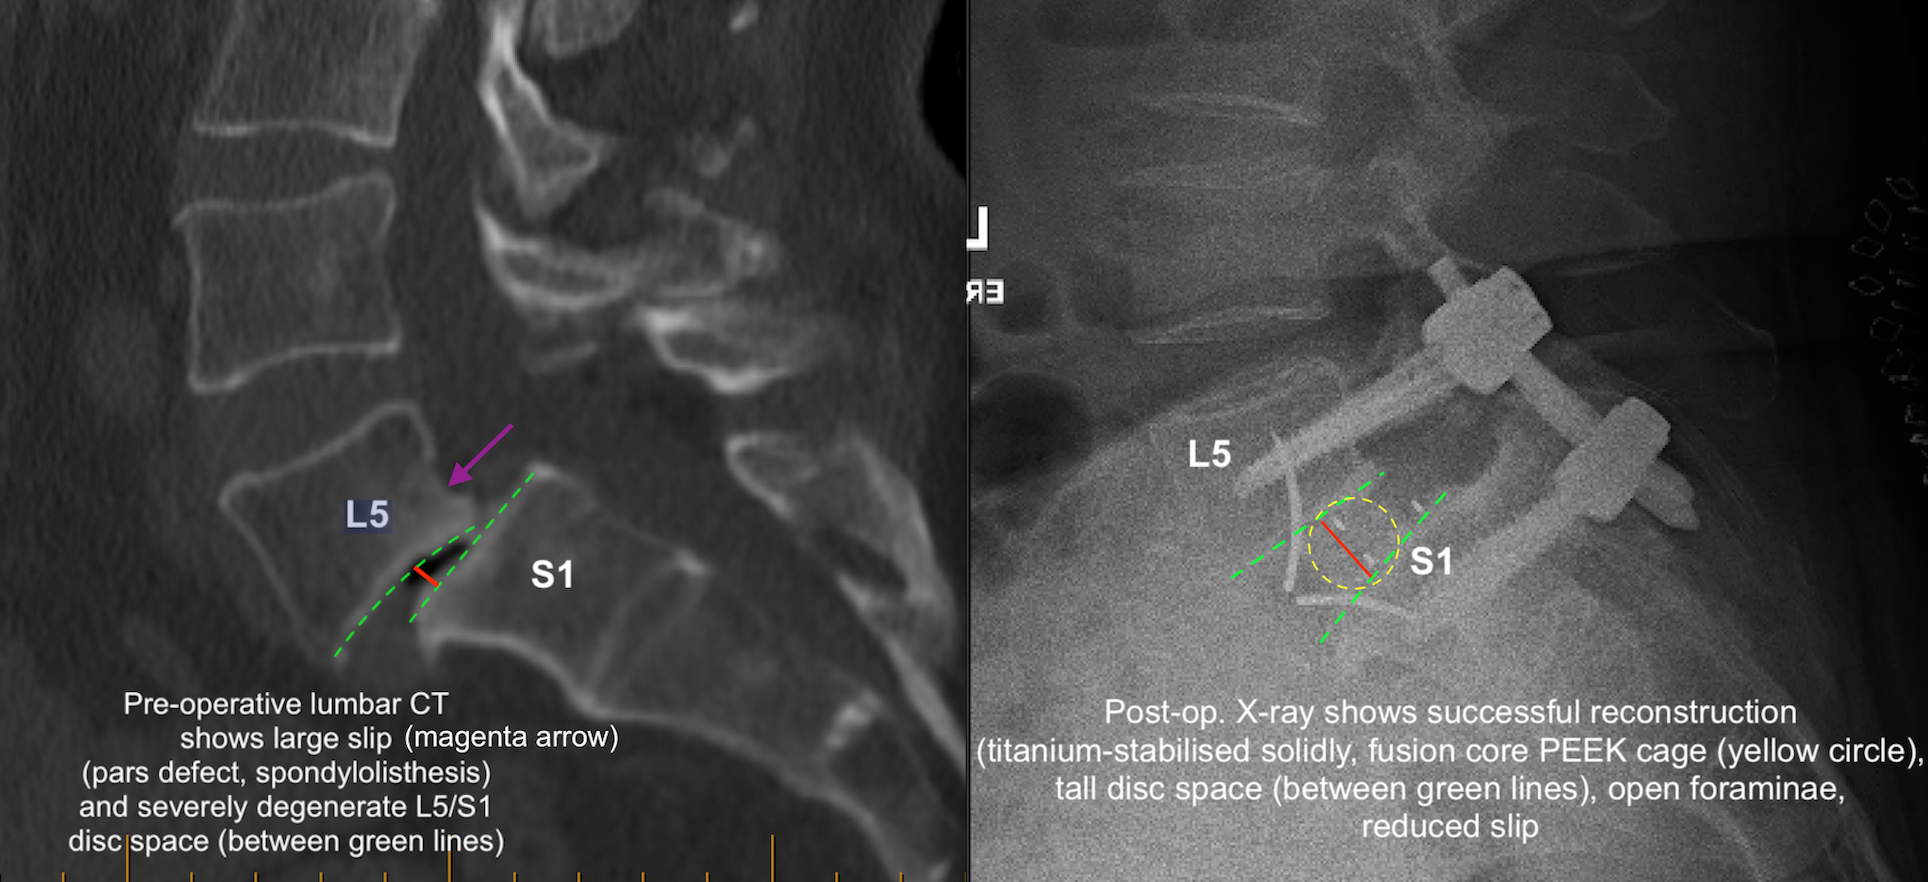

If there is a congenital (developmental) defect of a posterior stabilising structure of the spine called the pars interarticularis, then a spinal slip (spondylolisthesis) can arise from this “pars defect“. It usually becomes apparent in a person’s 30s to 40s, as the symptoms of low back pain +/- leg symptoms become more apparent and progress. Imaging then shows what the cause is (CT scan image below):

Sometimes the spondylolisthesis arises from severe degenerative changes affecting the stabilising facet joints. In such cases, the condition is referred to as “degenerative spondylolisthesis“.

The cage is then implanted and secured with integrated titanium blades or screws (see below; Stalif Midline II Ti shown). The disc height and the disc space angulation (lordosis) should be noticeably improved / restored, and the vertebral bone-framed ‘windows’ where the nerves come out at this level (the foraminae) should be more open now (i.e., indirect nerve decompression). If a person allows the discs to ‘deflate’ (desiccate/degenerate) enough over time, the vertebral body surfaces try to naturally fuse with one another (pseudoarthrosis), but the nerve windows get fused in the ‘closed’ position, which hurts the nerves (neuroforaminal stenosis or compression). Hence, restoring disc height via the ALIF procedure tries to stabilise the anatomy and keep those windows ‘open’ and their nerves ‘free’.

At some point following the above first stage, and usually during the same hospital admission, a second stage is carried out. This is in order to mechanically supplement/strengthen what has been done from the anterior approach, by way of “back-up” instrumentation. This adds to the stabilisation of this segment which is longstandingly anatomically deficient and naturally compromised. A standard posterior instrumentation is undertaken. This usually involves (in my own experience) posterior spinal midline exposure and then some form of guidance (e.g., mechanical/robotic, versus digital/image versus 3D-printed jigs) for transpedicular titanium screws which are lastly connected by titanium rods. Lamina-sparing spinal decompression and rhizolysis is usually carried out, with some local allograft fusion material laid down in the depths of the operative area.